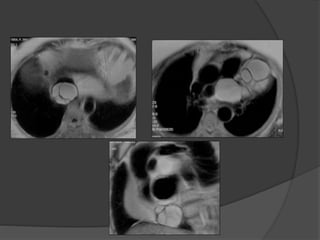

Case 1: 38 M with acute onset severe abdominal

pain

Cecum in the lesser sac

Diagnosis?

Cecum mildly dilatedCecum in the lesser sac between

the liver hilum and IVC

No twist to indicate cecal volvulus

Case 1 Diagnosis: Lesser sac hernia with cecal

incarceration

 Cecum large and distended

within the lesser sac

 Cecum and bowel viable

 Cecum and ascending colon

extremely mobile with no

lateral attachments

 Right colectomy done to

prevent recurrence

Surgery: